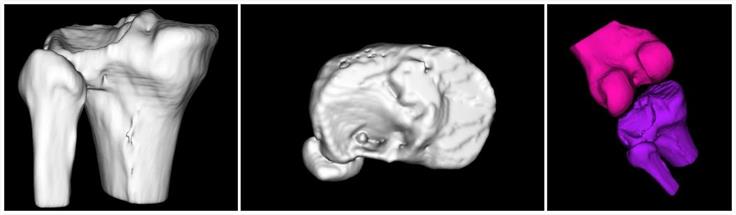

- 模擬病人骨折,讓醫生更直觀(guān)的了解骨折情況

- 軟件模擬手術(shù)入路,為醫生選擇最佳入路提供參考

該手術(shù)在軟件的輔助下確定以不剔除腓骨的方式進(jìn)行手術(shù)

- 數字模擬內植物選擇及放置位置

聞泰數字骨科專(zhuān)業(yè)軟件平臺已預設聞泰百得全部?jì)裙潭óa(chǎn)品和器械,方便術(shù)前規劃和內植入物選擇

- 3D打印的骨折模型實(shí)物,供醫生進(jìn)行手術(shù)模擬、內植物選擇、提前預彎,使板型更貼合患者

我們的解決方案提供多樣的3D打印技術(shù),包括熱熔沉積技術(shù)(FDM),光固化技術(shù)(SLA)和激光燒結技術(shù)(SLS),可提供不同材質(zhì)、不同尺寸、不同精度和不同打印速度的多種3D打印選擇。